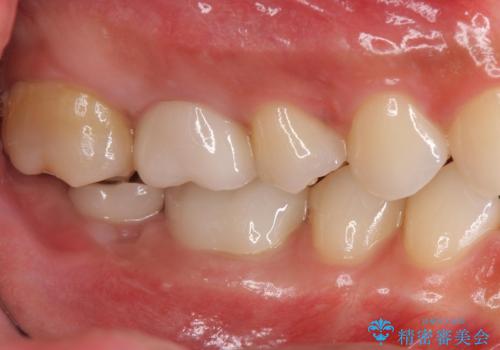

- 右下の奥歯がない状態でしばらく過ごされていた方です。

インプラント入れて噛めるようにしたいとのことだったため、治療を行います。

向かい合わせになる歯が歯茎と噛んでいるため、歯茎の厚みも調整していきます。